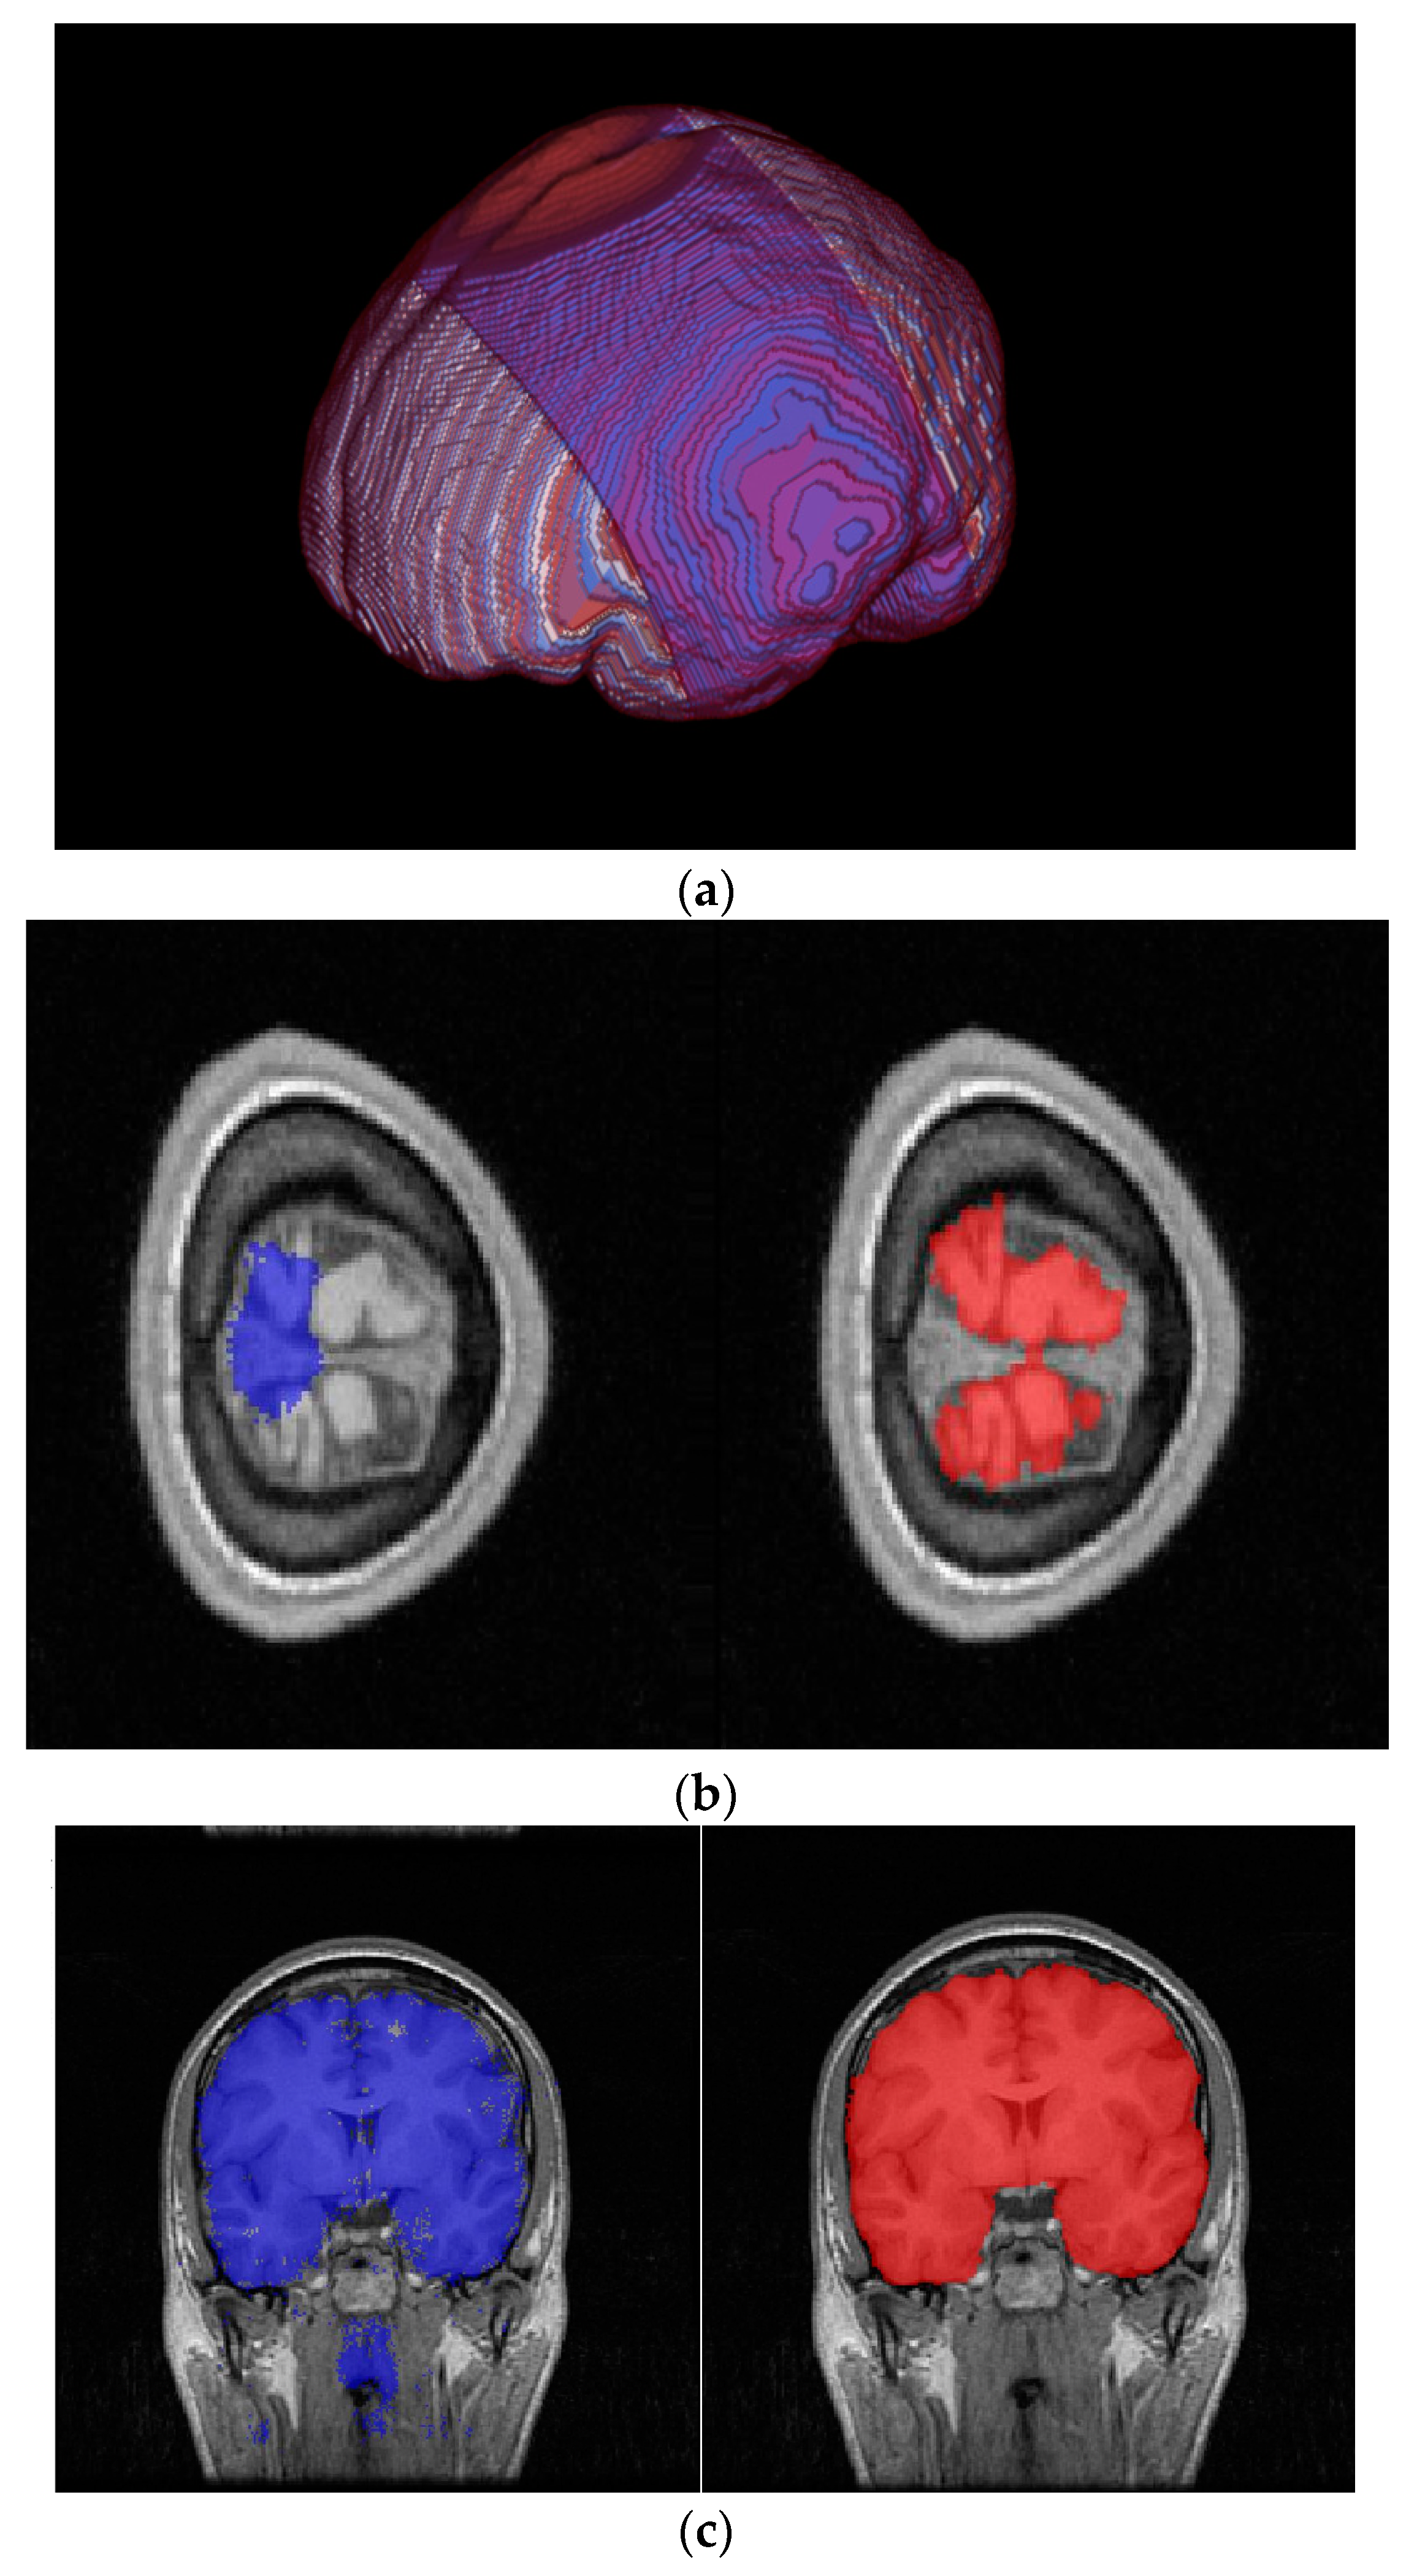

2.2. Full Image Information Mining with a K-Means Cluster Preprocessing

2.3. Hybrid-U-Net Framework

2.4. Dimensionality Reduction U-Net for 3D MRI Data